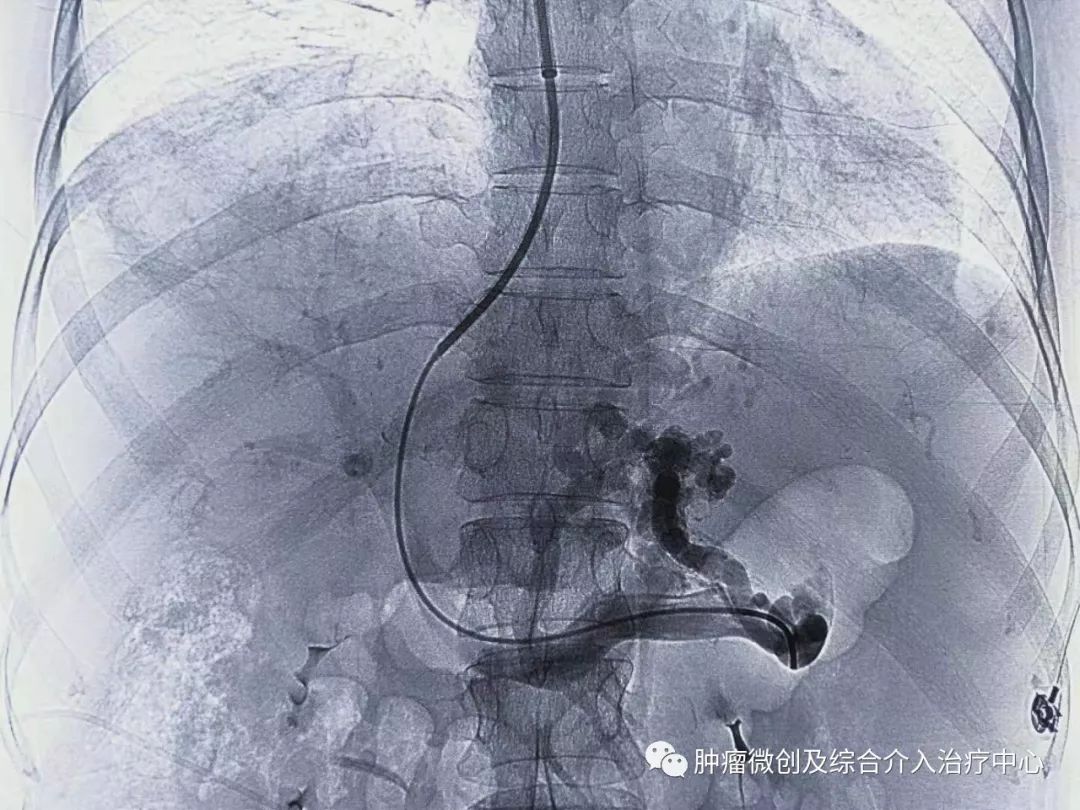

手术过程:

经过静脉穿刺进入门脉系统:

栓塞消化道出血责任血管:

再次造影可见:门脉血流流向-体静脉达到分流目的,术前侧压力42,术后25,门脉压力明显降低,达到防止再次出血目的。